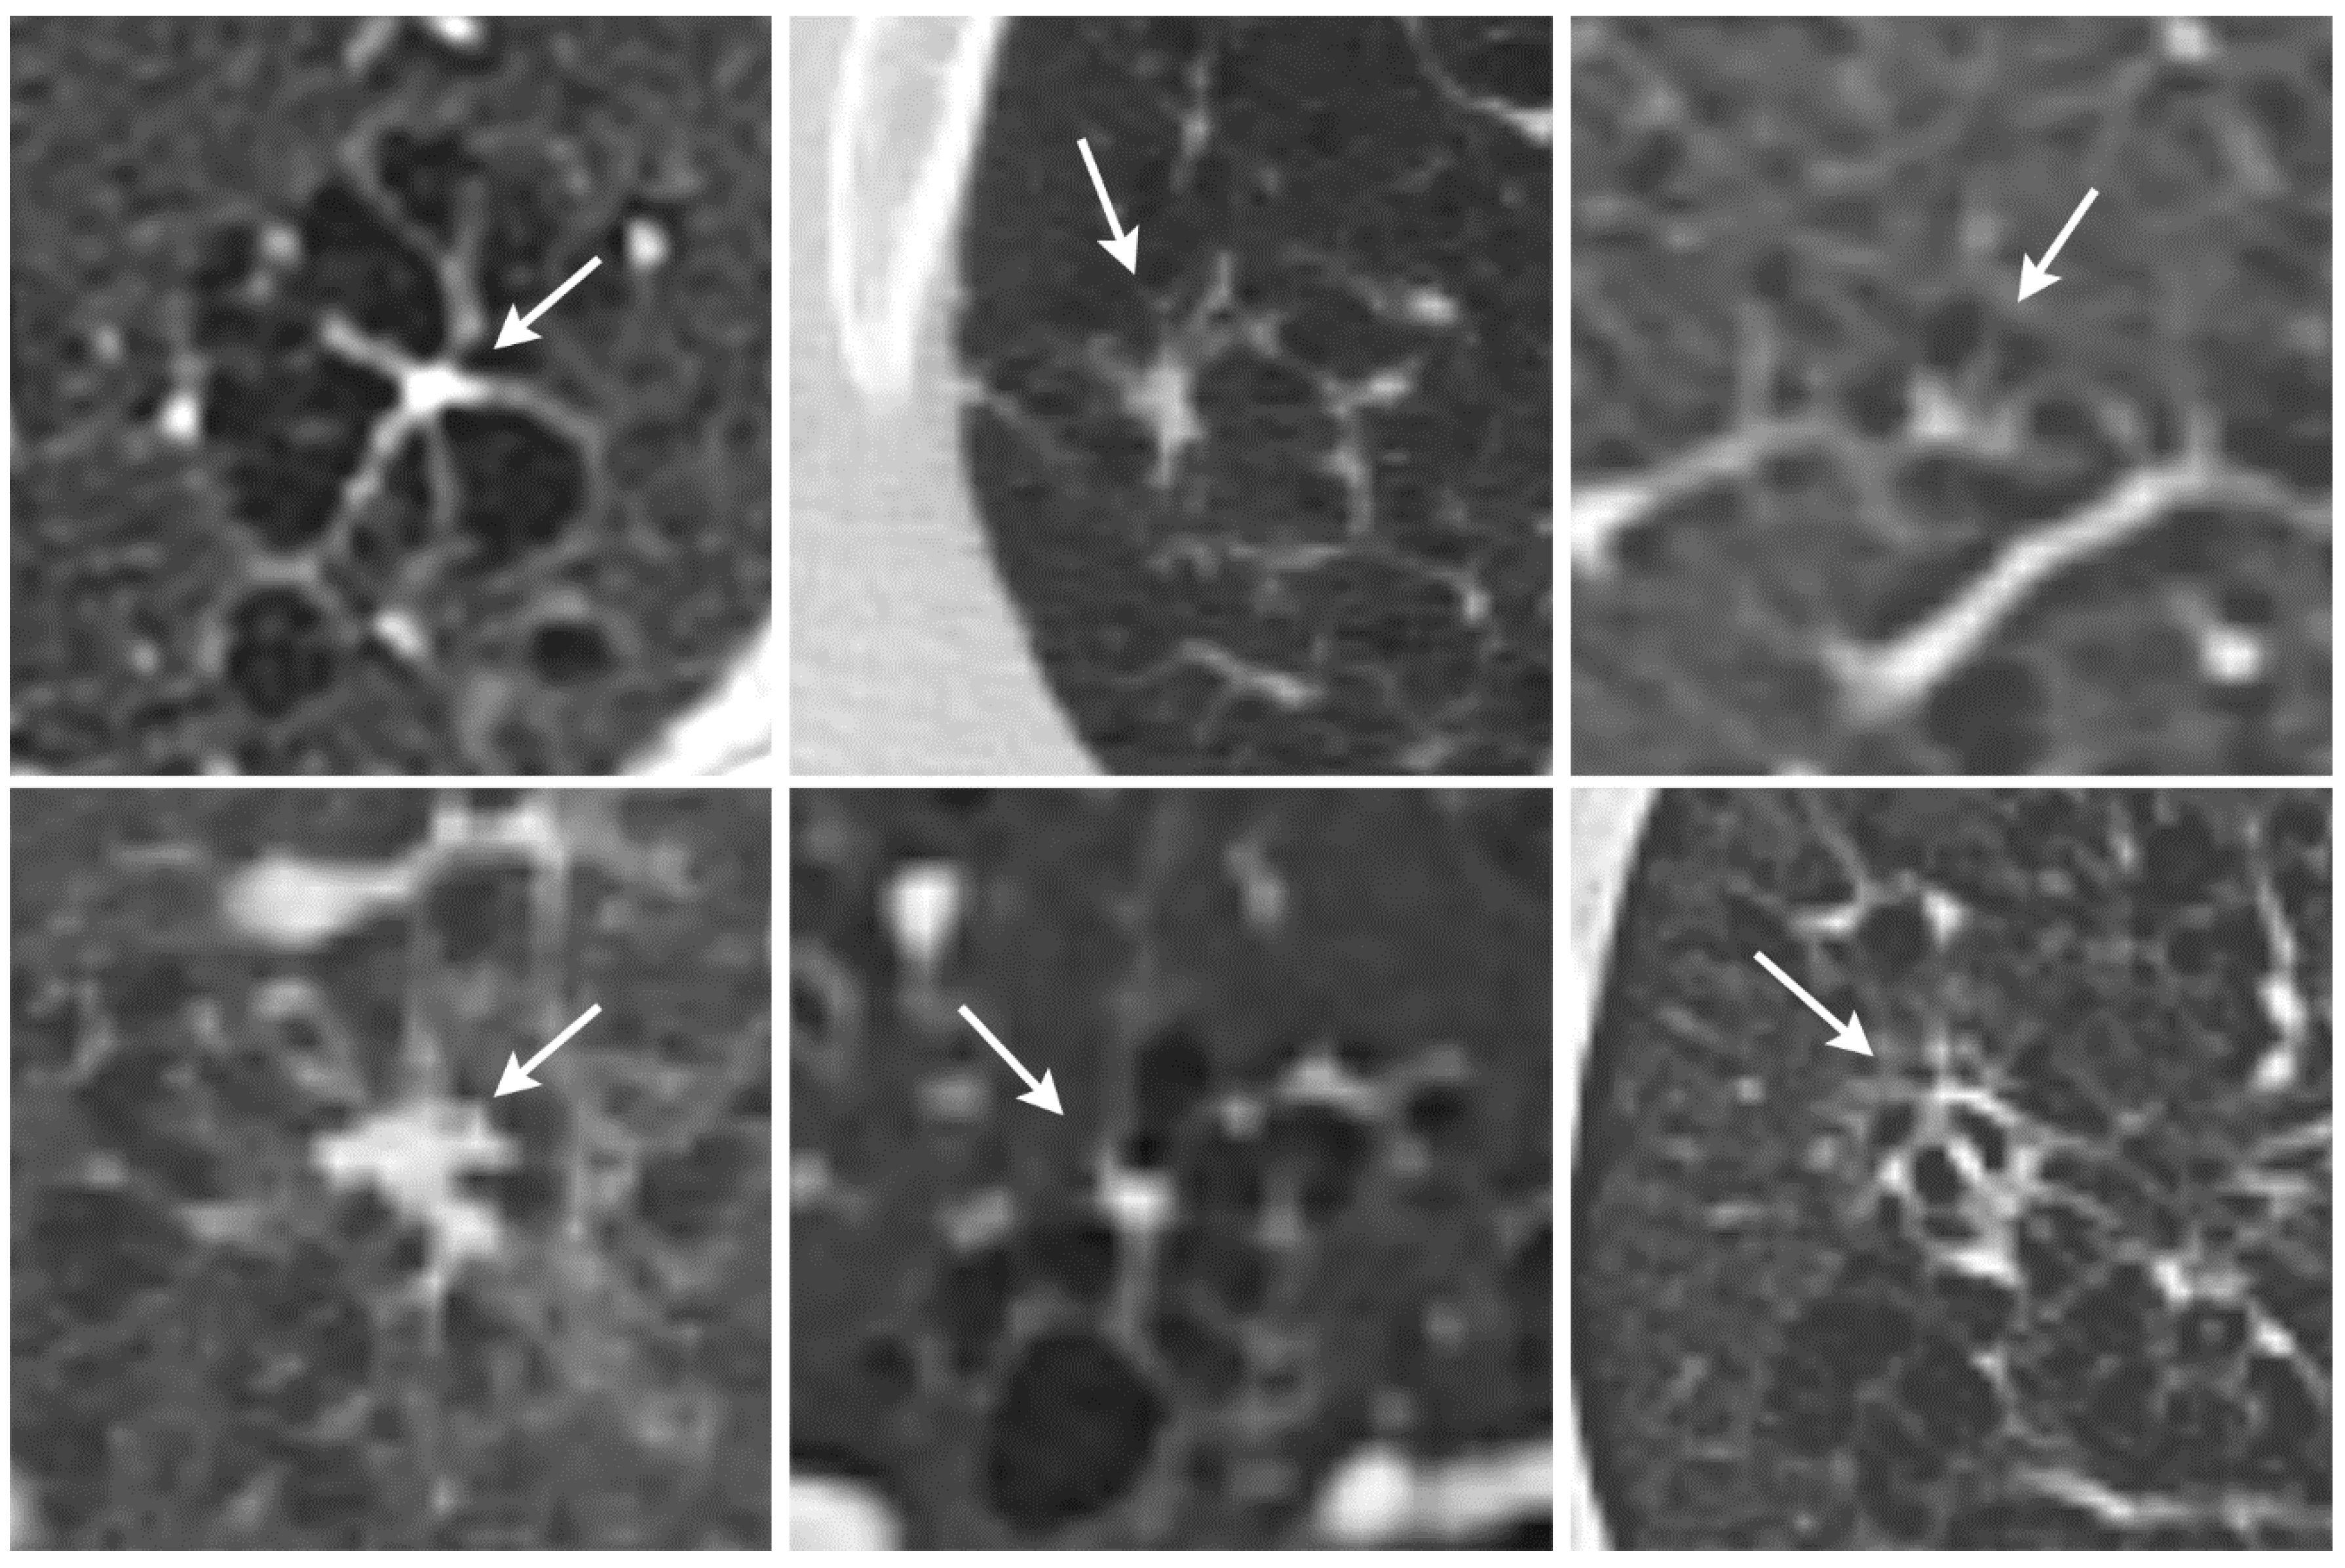

We identified a previously undescribed HRCT finding in patients with PLCH for which we propose the term octopus sign (Figure 1). PLCH is a smoking-related lung disease with still unclear pathogenesis. Various molecular mechanisms have been identified that underlie the pathogenesis and progression of the disease [5]. One of the characteristics of early, cellular PLCH is an accumulation of a large number of CD1a+ Langerhans cells in loosely formed bronchiolocentric sheets and ill-defined clusters [5,16]. With time, the cellular infiltrates are replaced by scaring fibrosis, leading to traction and, thus, architectural distortion of the lung parenchyma [16,17,18]. These changes are well detectable in histopathology, as they form stellate or octopus-like lesions [13,18]. Due to the comparatively large size of several millimeters in diameter, we hypothesized that these lesions should be visible on HRCTs.

Figure 1. Correlation of the “octopus sign” on histology and HRCT. The histological specimen shows a fibrotic Langerhans cell histiocytosis lesion with a central, peribronchiolar fibrosis extending into the periphery, resulting in architectural distortion with traction emphysema (hematoxylin and eosin staining). The septal extensions of the lesion resemble tentacles of an octopus. The HRCT of the same patient also showed lesions that were similar in shape to an octopus.

Figure 2. The octopus sign (arrows) in six different patients with Langerhans cell histiocytosis (stage 2).